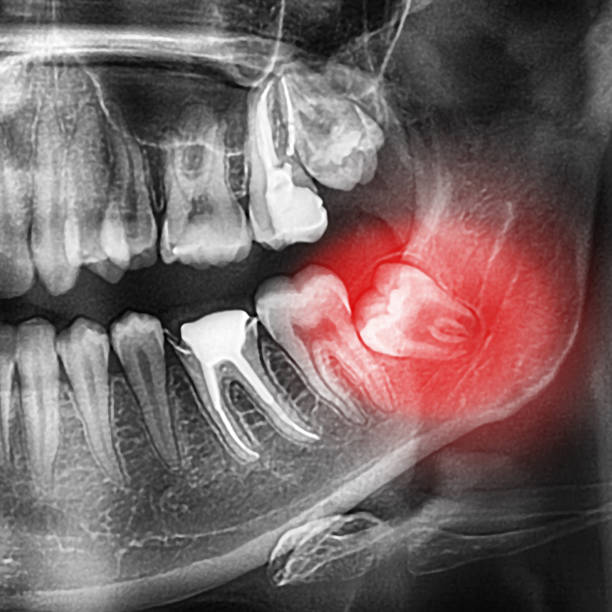

사람은 평생 동안 52개(유치 20개, 영구치 32개)의 치아가 나온다. 그 중 사랑니는 가장 늦게 나오는 영구치이자, 가장 안쪽에 나는 큰 어금니이다. 위·아래 양쪽으로 하나씩 총 4개가 날 수 있지만 개인차가 있다. 사랑니가 문제가 되는 주된 이유는 턱뼈가 작아져 사랑니가 자리 잡을 공간이 부족해지다보니, 치아가 잇몸 속에 매복돼 있거나 일부만 나오거나, 정상적인 위치에 나오지 않는 경우가 많기 때문이다.

관리를 잘 할 수 있다는 가정하에 그리고 사랑니가 정상적인 위치에 반듯하게 나와 있고 칫솔질을 통해 청결하게 관리할 수 있다면 굳이 뽑을 필요는 없다. 하지만 사랑니는 제일 안쪽에 위치해있기 때문에 칫솔질 등의 위생관리가 어려우며, 음식물이 잘 끼어 구취나 충치, 잇몸질환 등의 문제가 발생하기 쉽다. 일부만 나와 있는 사랑니의 경우, 제대로 관리하지 않으면 잇몸의 감염이나 주변 치아의 충치, 흡수를 일으키기도 하며, 심한 경우에는 영구적인 손상(턱뼈 흡수, 감각마비, 안면비대칭 등)이 생길 수 있다.

잇몸 속에 매복된 사랑니, 별다른 통증이 없는데도 발치해야 하나?

발치 하는 것이 좋다. 사랑니가 잇몸 속에 완전히 매복되어 있다면, 염증을 일으키거나 주변 치아를 손상시키지는 않지만, 언제든지 문제를 유발할 수 있기 때문이다. 사랑니가 나오기 시작하는 18세 전후로는 특별한 통증이 없고, 육안으로 사랑니가 보이지 않더라도 치과에서 검진을 받아보는 것이 좋다. 사랑니가 있는 것이 확인되면 바로 발치하는 것을 추천하지만, 발치하지 않고 남겨두는 경우에는 치과에 주기적으로 방문하여 매복된 사랑니 상태와 변화여부를 관찰하는 것이 좋다.